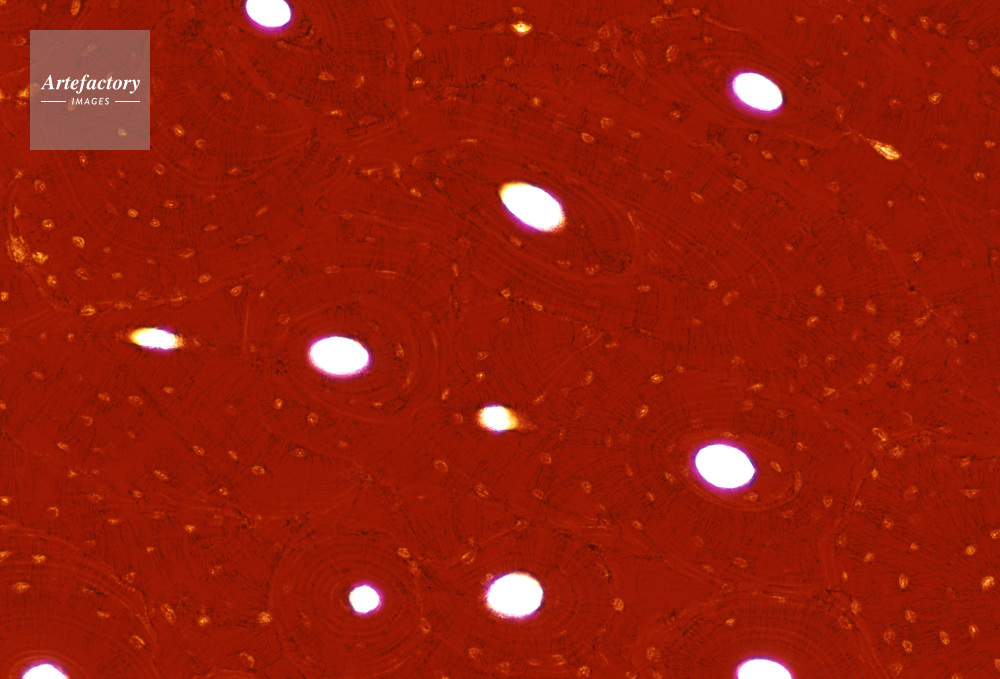

| キャプション | 硬骨,人間,100倍,横断面 | 制限事項 | ||

| ソース | ピクセル数 | 5556px × 3772px | ||

| 撮影地 | 印刷サイズ | 30.3cm × 20.6cm | ||